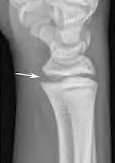

A 35-year-old woman reports wrist pain after a fall onto an outstretched hand. On exam, she has focal tenderness over the wrist snuffbox. A radiograph and CT image are shown in Figures A and B. What is the proper treatment of her injury?

Contrast enhanced MRA of the wrist is typically used to diagnose hypothenar hammer syndrome or other vascular abnormalities.